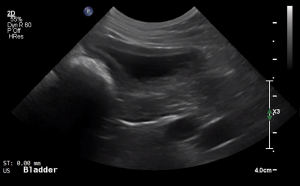

SIMON Ultrasound Database

This ultrasound database is a free resource for students and doctors!

Our collection includes videos of dogs, cats, horses, cows, humans, and many other species!